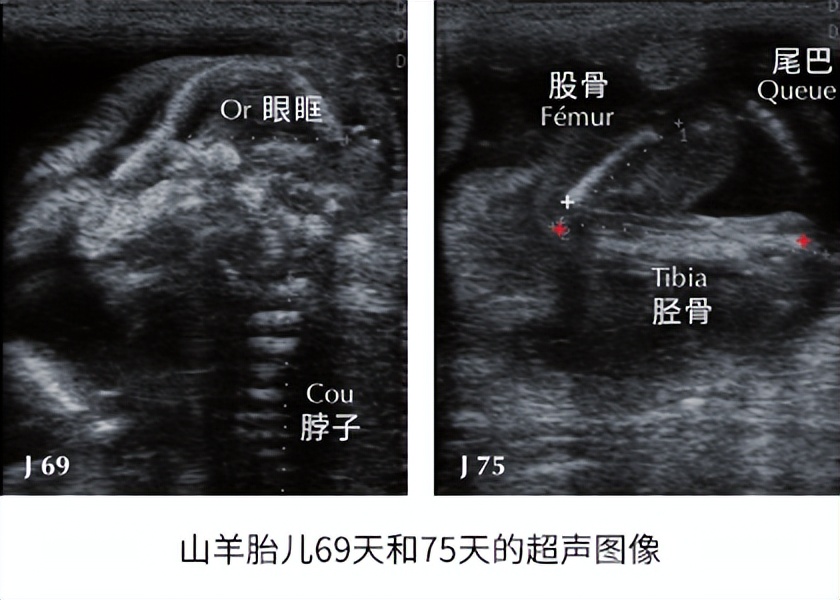

股骨、胫骨和肱骨的长度可以很好地估计配种后第 50 天至 146 天之间的妊娠阶段。 然而,由于难以接近并且不同骨骼之间可能存在混淆的风险,因此很少使用它。

测量眼眶直径是一个很好的测胎龄方法(R 2 ≥ 0.80); 最好在妊娠第 50 天至 126 天之间进行。